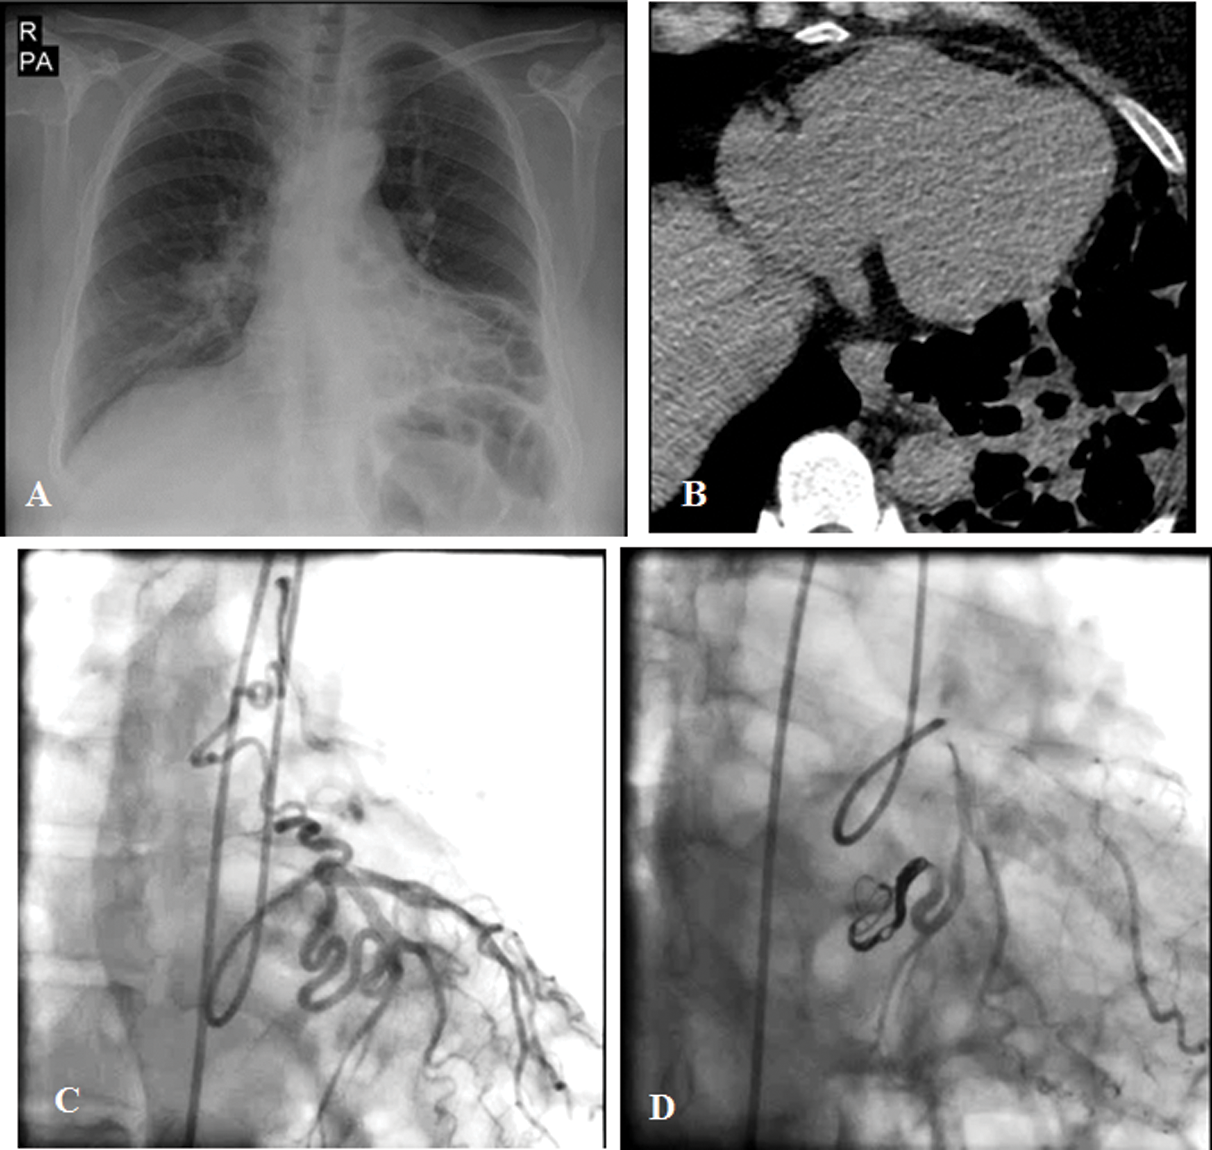

A 63-year-old woman with a history of exertional dyspnea and several episodes of hemoptysis of 3 months’ duration referred to our hospital (Tab. 1). Chest radiography and lung spiral CT scan showed left lower lobe bronchiectasis (Fig. 4). TTE revealed normal LV size with a good systolic function (LVEF = 55%), mild RV enlargement, and no valvular abnormality. Coronary angiography showed an anomalous vessel from the LCx to the left pulmonary artery, which was subsequently closed successfully via the arterial access (the femoral artery) with 3 coils (8 mm × 30 cm Axium Helix [Covidien, USA], 8 mm × 30 cm Stryker Neurovascular [Target, 360 Ultra, GB Tech USA Inc.], and 6 mm × 10 cm [Target, 360 Ultra, GB Tech USA Inc.] with no residual shunt (Fig. 4). At 1 month’s follow-up, TTE and CTA showed complete closure with no residual shunt.

Figure 4: The chest radiograph and lung spiral computed tomography scan show left lower lobe bronchiectasis (Figs. A and B). The coronary angiogram illustrates an anomalous vessel from the left circumflex artery to the left pulmonary artery (Fig. C), which was successfully closed via the femoral artery access with 3 coils, with no residual shunt (Fig. D)